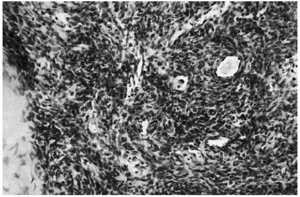

Se realizó una extirpación quirúrgica de la lesión. El estudio histopatológico mostró una tumoración dérmica multilobulillar con una zona central hipocelular, esclerosa y otra hipercelular en la periferia en la que se veían multiples espacios vasculares (fig. 2). Estas áreas más periféricas de espacios vasculares ramificados recordaban a un hemangipericitoma, y se continuaban insensiblemente con nódulos esclerosos. También se observaban nódulos hemangiopericitoides a distancia y sin conexión aparente con la tumoración principal (fig. 3).

Fig. 3.--Detalle de un nódulo de aspecto hemangiopericitoide que contiene múltiples espacios vasculares. Localizado a cierta distancia de la tumoración principal.